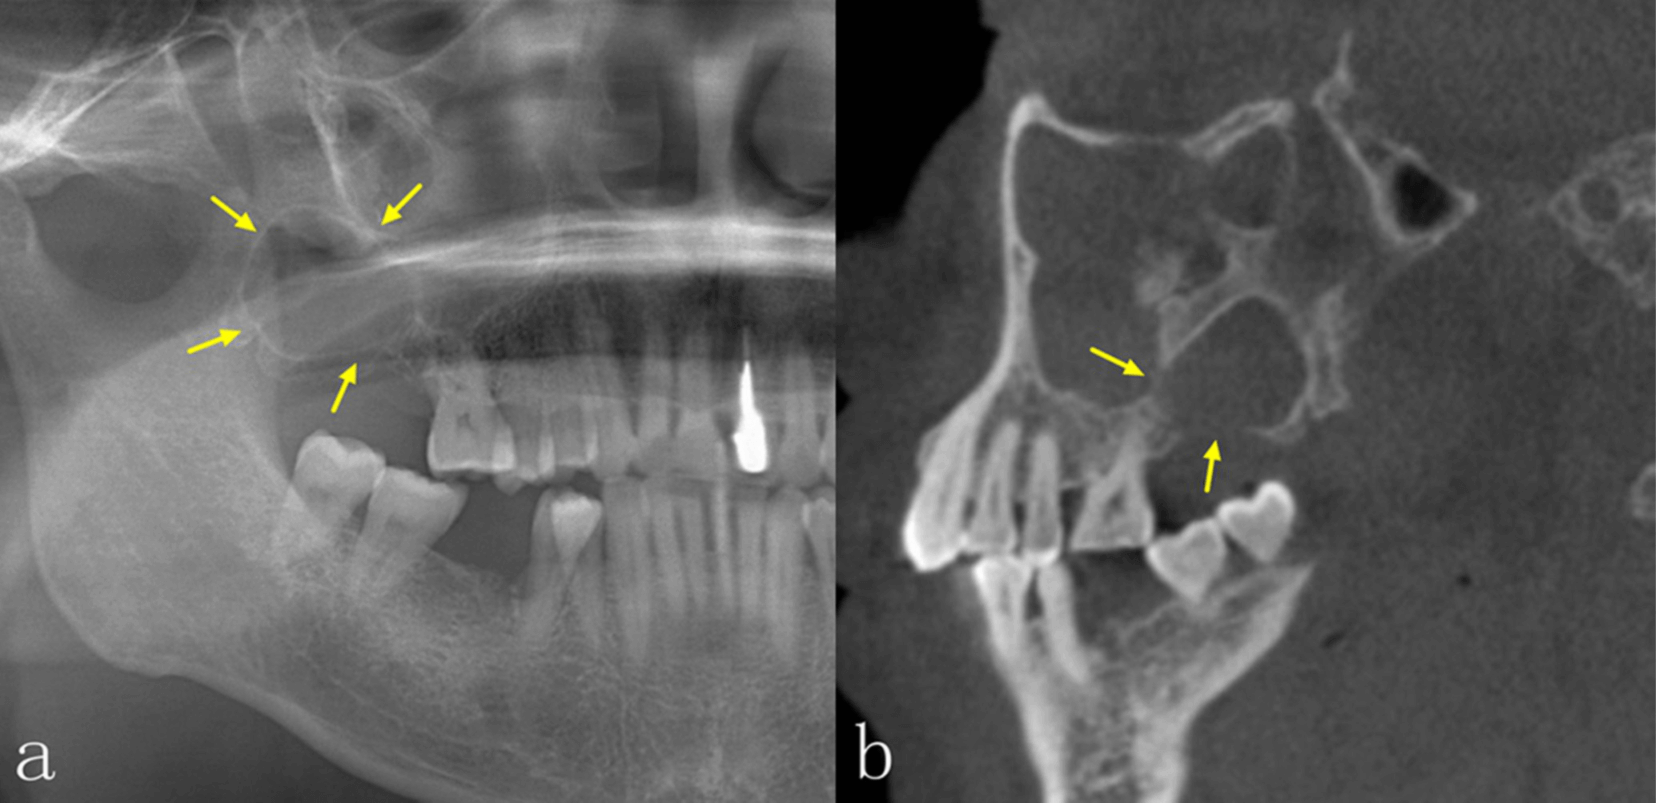

La radiografía panorámica (PAN) y la tomografía computarizada de haz cónico (TCCB) son dos modalidades radiográficas utilizadas en el diagnóstico, la planificación del tratamiento y el manejo de las enfermedades orales y maxilofaciales. No solo muestran las características de las lesiones en las imágenes, sino que también guían a los médicos para que realicen los diagnósticos más adecuados, así como los planes de tratamiento posteriores, y para supervisar la curación y/o la recurrencia de la enfermedad durante el seguimiento. La PAN, como técnica de imagen más común, puede proporcionar una visión general de las mandíbulas y la dentición, pero las estructuras anatómicas y las lesiones en las mandíbulas anteriores no están bien definidas debido a la superposición de las vértebras cervicales. Además, la calidad de la imagen de la PAN puede verse influenciada por la superposición de las estructuras anatómicas circundantes, las sombras de aire, las imágenes fantasmas y la sensibilidad a los errores de posicionamiento del paciente. Estos errores también darán lugar a una distorsión de la imagen y a un aumento desigual en las dimensiones horizontal y vertical. La CBCT, que se ha introducido ampliamente en la imagenología maxilofacial desde finales de la década de 1990, tiene ventajas sobre la PAN bidimensional PAN bidimensional, debido a su naturaleza tridimensional. La CBCT no solo muestra las estructuras anatómicas y las lesiones en los planos axial, coronal y sagital, sino que también permite realizar una variedad de efectos de posprocesamiento.

Es bien sabido que la TCCB presenta numerosas ventajas en el diagnóstico de enfermedades orales y maxilofaciales. En comparación con la PAN, la TCCB puede proporcionar más información para ayudar a los odontólogos a realizar diagnósticos, diseñar planes de tratamiento y supervisar los seguimientos postoperatorios. Actualmente, hay una escasez de estudios que se centren en las diferencias de las características radiográficas entre la PAN y la TCCB para obtener imágenes de las lesiones intraóseas de la mandíbula mediante un método cuantitativo. El estudio más reciente, con 31 casos incluidos, mostró que, aunque había diferencias en el aspecto radiográfico de las lesiones intraóseas en la PAN y la TCCB, la TCCB no ayudaba a mejorar la precisión del diagnóstico. Los autores concluyeron que el bajo número de casos de su estudio era una limitación. Por lo tanto, los objetivos de este estudio, que utilizó un mayor número de lesiones, fueron: investigar las diferencias en las características de imagen de las lesiones intraóseas de la mandíbula entre PAN y TCCB; y determinar con mayor precisión la eficacia diagnóstica de las dos modalidades radiográficas en la evaluación de las lesiones intraóseas de la mandíbula.

Las diferencias significativas en el aspecto radiográfico de las lesiones intraóseas entre la PAN y la TCCB se observaron en la integridad de los bordes corticales, la expansión de los límites anatómicos circundantes, el adelgazamiento cortical, la destrucción cortical y la reabsorción radicular, especialmente en las regiones anteriores de ambos maxilares y en el maxilar superior. La TCCB también mejoró la precisión diagnóstica, especialmente en las lesiones del maxilar superior. Los radiólogos se mostraron más seguros al utilizar TCCB en comparación con PAN. Estos hallazgos podrían utilizarse en el desarrollo de directrices para la obtención de imágenes de patologías intraóseas en los maxilares.